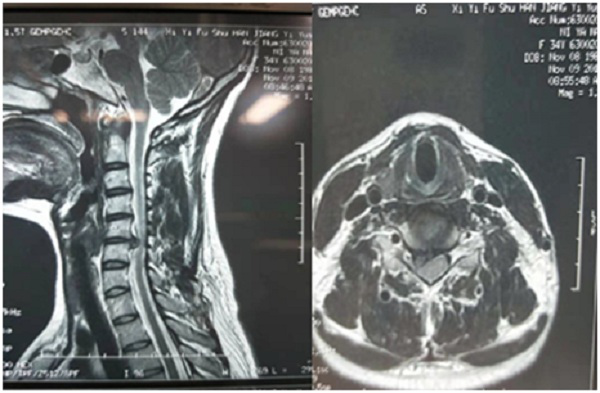

患者,女性,34岁,以“颈肩部疼痛伴右上肢抽痛、麻木1周”主诉入院,右上肢抽痛、麻木较重,尤其夜间疼痛难忍,VAS评分8分,常规保守治疗及康复理疗无缓解,常需要大量止痛药物及镇静药物治疗。

MR:颈5/6椎间盘右旁中央型突出

经过病情讨论,诊断为神经根型颈椎病,颈5/6椎间盘右旁中央型突出,神经根受压,适宜手术治疗,摘除突出髓核、神经根减压。结合患者情况,单阶段颈椎间盘突出,决定行微创椎间孔镜手术治疗。该手术具有手术切口微小,术中软组织损伤较小,出血较小,术中可视下操作,损伤风险较小,不需要椎体间融合固定,术后恢复较快等优点。